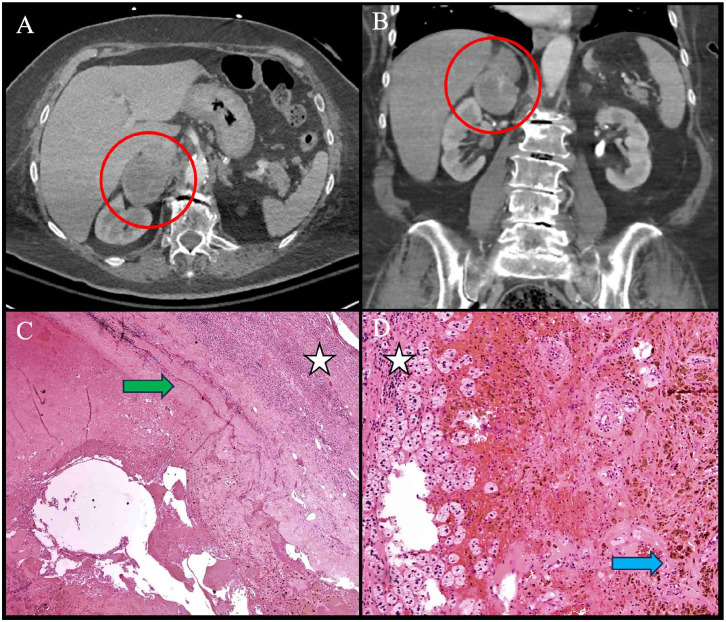

Incidental adrenal cysts are quite rare and thus can present a diagnostic conundrum for even experienced clinicians. Here, we present the case of a patient with an incidentally identified 5 cm adrenal mass. Her evaluation was notable for evidence of mild autonomous cortisol secretion and imaging findings concerning for malignancy with possible invasion of the inferior vena cava. Adrenalectomy was performed; pathology ultimately demonstrated an adrenal cortical pseudocyst without evidence of malignancy. All patients with solid, high-density, or large adrenal tumors require further imaging for characterization and biochemical testing for hormone secretion. While simple, low-density adrenal adenomas and cysts do not require further imaging evaluation beyond non-contrast CT, mixed cystic and solid lesions or pseudocystic lesions should be evaluated similarly to solid tumors, with the caveat that pseudocysts cannot always be well-differentiated from benign cysts on imaging. All adrenal incidentalomas should be evaluated with a biochemical work-up to assess hormonal activity. Tumors suspicious for malignancy require surgical excision. Patients with benign, hormonally active tumors should be managed surgically or medically, according to their primary pathology.